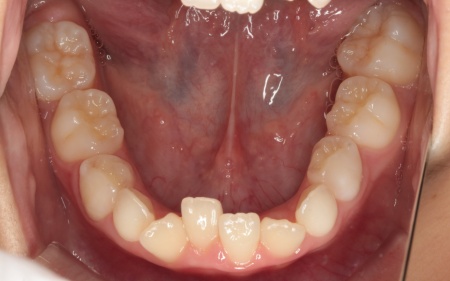

10歳女の子 顎の幅を広げる装置とマウスピース型の矯正装置で反対咬合を改善した症例

拝見したところ、上前歯が下前歯の内側に入り込む「反対咬合(こうごう)」が認められました。

詳しい検査の結果、患者様の反対咬合は歯の位置の問題ではなく、上顎の発育が十分ではないことが主な原因と考えられます。

まずは、「バイオブロック」による治療で上顎の発育を促すこと、その後、前歯の位置を細かく整えるためマウスピース型矯正装置「インビザラインファースト」と、上顎を前方へ引き出す「前方牽引装置」を併用する治療計画を提案しました。